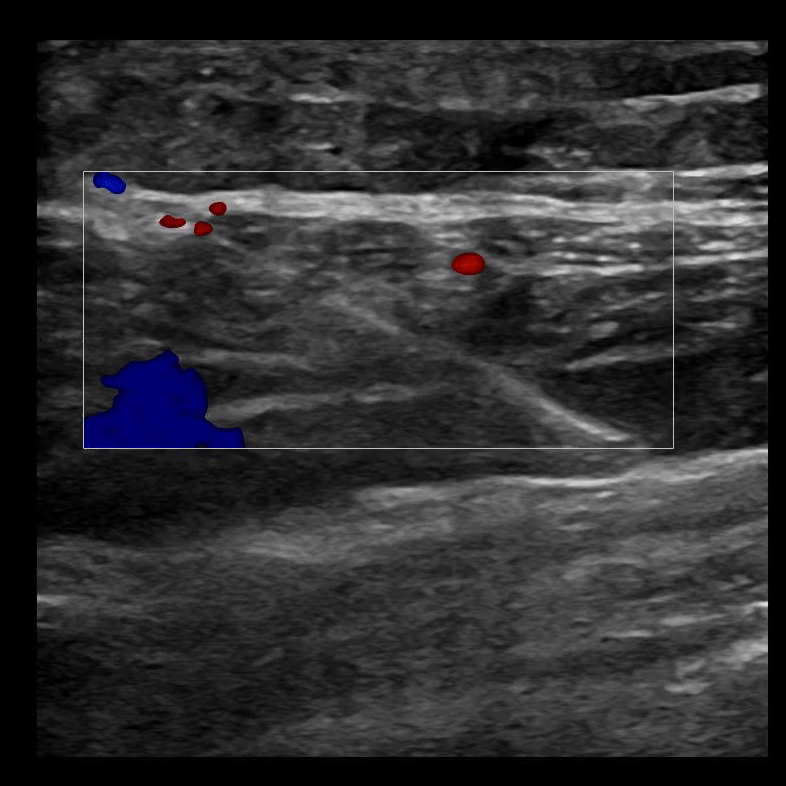

SAPB 4: Unzipping of the latissimus dorsi and serratus anterior muscles with hydrodissection.

SAPB 5: Anesthetic is deposited in the fascial plane between the latissimus dorsi muscle (superficial) and the serratus anterior muscle (deep).

SAPB 6: The ability to follow your needle tip in long axis is an absolute necessity, because deep to the serratus anterior muscle lies rib and pleura.

SAPB 7: The serratus anterior plane block deposits anesthetic in the plane between the latissimus dorsi muscle superficial to it and the serratus anterior muscle deep to it. If done correctly, the two muscles will unzip, or seperate, from each other.